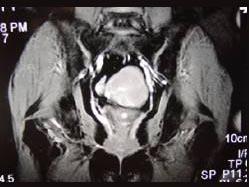

问题 55岁女性患者,绝经后阴道排液半年余,行MRI检查,如图所示,最佳答案是 ( )

选项 A、子宫肌瘤 B、子宫内膜癌 C、子宫颈癌 D、正常子宫 E、子宫内膜异位症

答案 B